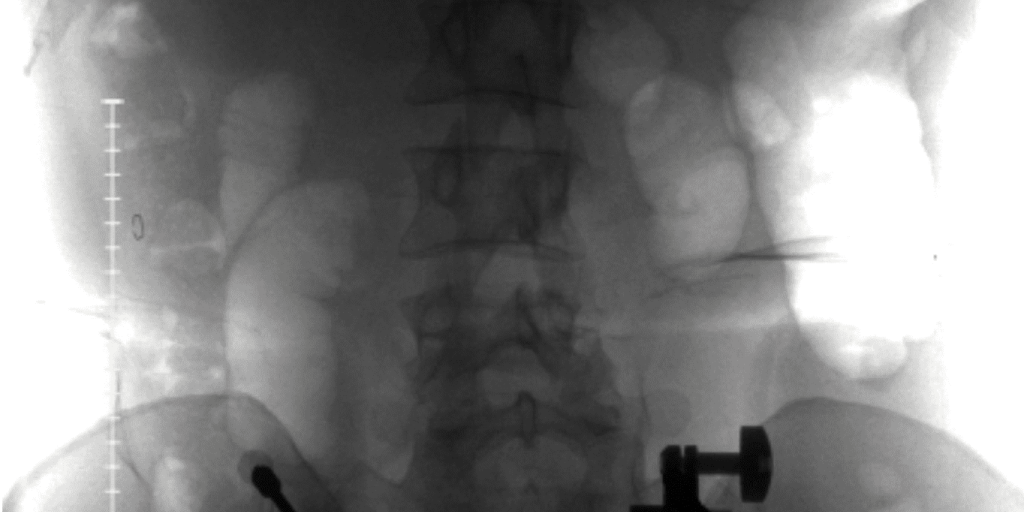

The Day My Spine Shattered—and the Surgeon Who Rebuilt It – Social Lifestyle Magazine

A Spine Surgery Survivor’s Journey Through Trauma, Trust, and the Science of HopeYou don’t think about your spine—until it’s the only thing you can think about. That moment came...